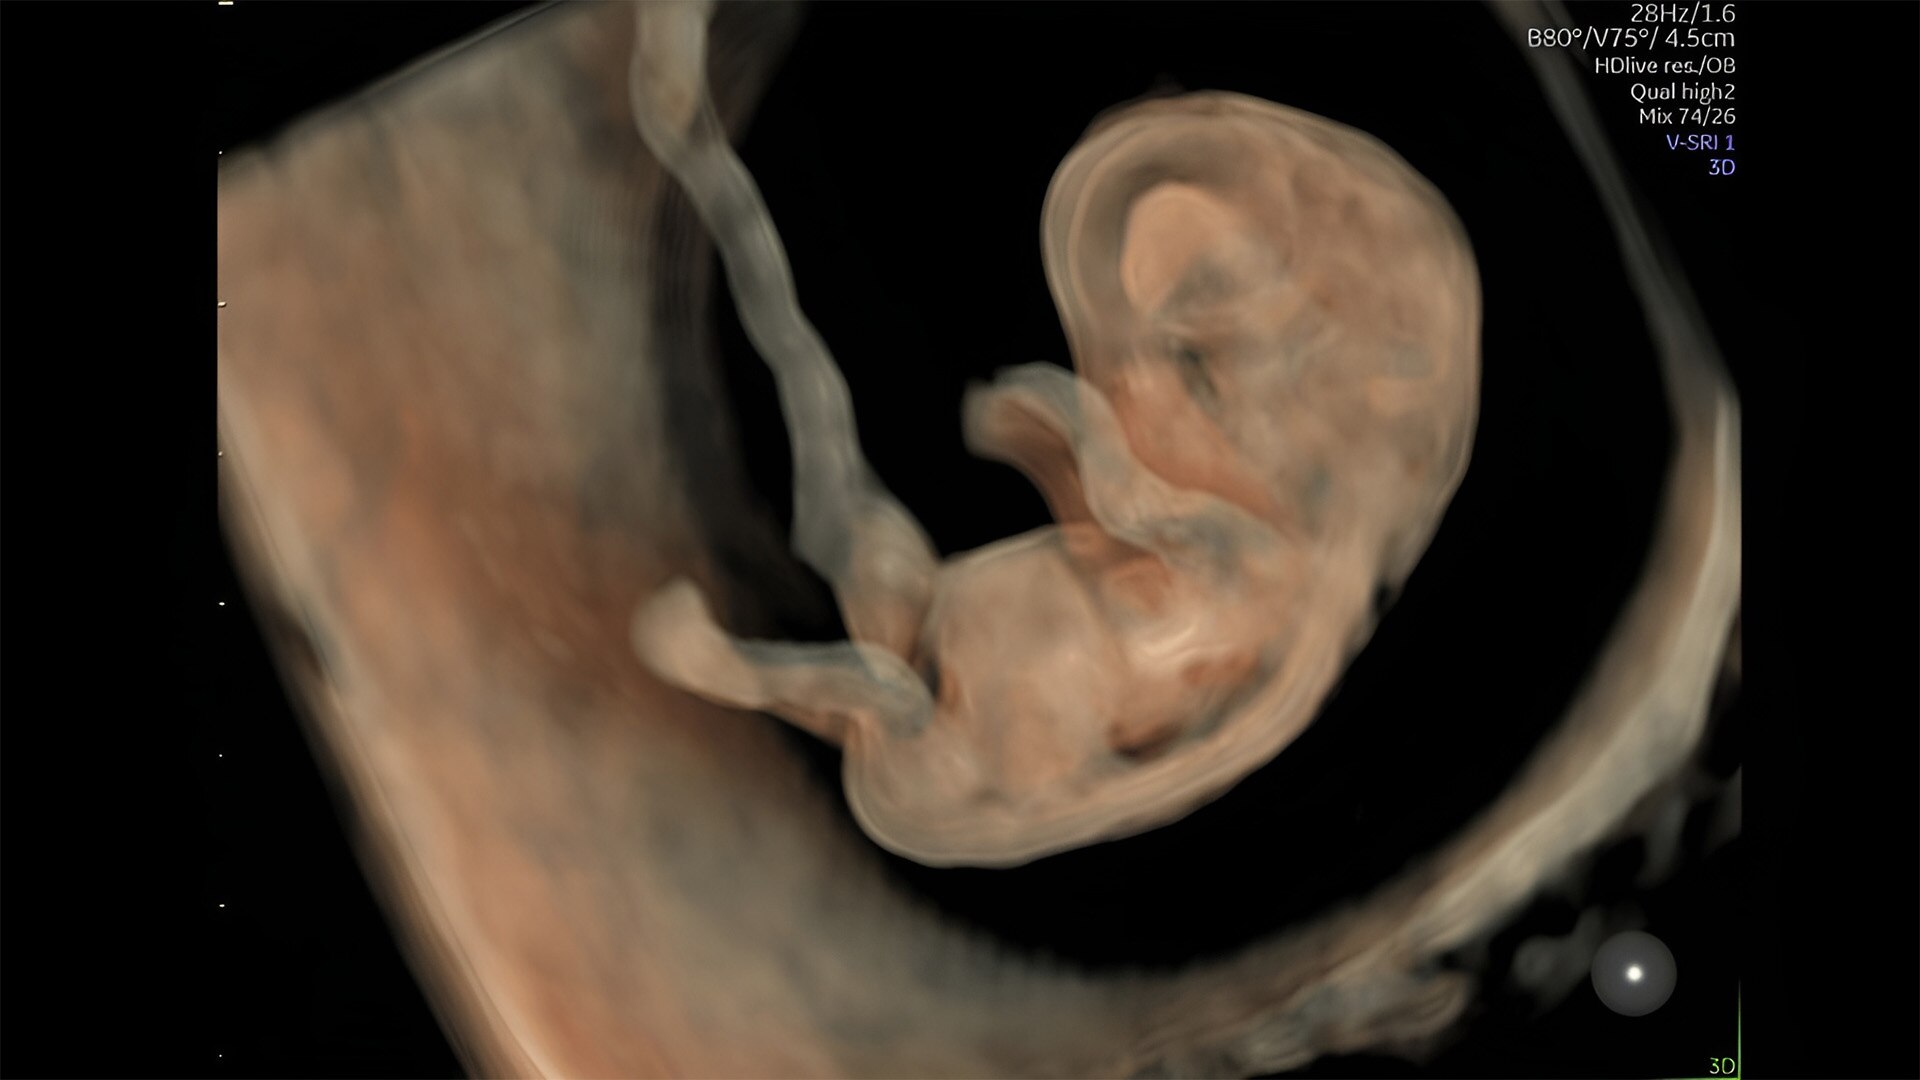

First trimester exams

Perform detailed exams with high-resolution for early insights to fetal health